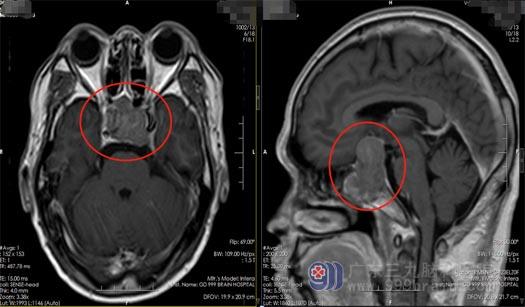

54岁的杨先生一年前开始出现左眼模糊,视野缺损,在当地医院进行检查发现鞍区占位;近两个月病情不断加重,并出现了头痛症状。没想到在广东三九脑科医院进行了一系列检查后发现:颅内巨大垂体瘤。

找出了原因,可杨先生又增加了新的担忧,毕竟开颅手术是高风险的治疗。针对患者及家人的顾虑,神经外五科的医生团队为杨先生制定了微创治疗方案,将一外径为筷子粗细的内镜插入患者鼻孔,把肿瘤从鼻子里“夹”出来。11月10日,杨先生经鼻蝶鞍区行巨大垂体瘤切除术,应用神经内镜,借助鼻腔内的微小切口,直视下避免了颈内动脉、视神经、垂体柄等重要结构的损伤;细致地暴露、分离和切除,整个手术过程清晰地显示在高清电视屏幕上,非常流畅、顺利地全切了肿瘤,完好地保护了视神经、下丘脑、颅底动脉等重要结构。术后,杨先生的左眼视力和术前比较有好转,没有出现视力视野缺损。